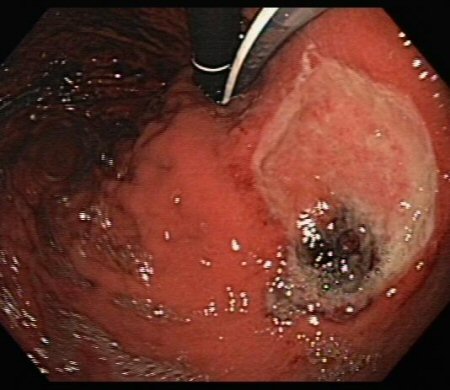

Large gastric ulcer with large, protuberant visible vessel

From the collection of Douglas G. Adler, MD